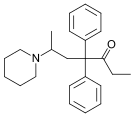

| Opioid peptides | Skeletal molecular images |

|---|---|

| Adrenorphin |  |

| Amidorphin |  |

| Casomorphin | |

| DADLE | |

| DAMGO |  |

| Dermorphin | |

| Endomorphin |  |

| Morphiceptin |  |

| Nociceptin |  |

| Octreotide |  |

| Opiorphin |  |

| TRIMU 5 |  |